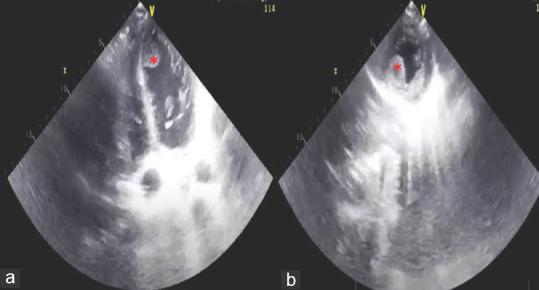

Left ventricular (LV) thrombus is a known complication of acute myocardial infarction (AMI), especially anterior wall MI and leads to systemic thromboembolism. However, increase in the rates of coronary perfusion either by thrombolysis or percutaneous interventions have reduced its incidence. Concurrent stroke and MI are seen in 0.009% of cases. The occurrence of AMI with LV thrombus with or without stroke mandates the combination of antiplatelet and antithrombotic therapy. Hitherto, there are no randomized studies in the setting of AMI with LV thrombus comparing dual (single antiplatelet plus oral anticoagulant [OAC]) and triple therapy (dual antiplatelet therapy with OAC). There are no large randomized trials as well to delineate the optimal therapy for simultaneous cardiac and cerebral infarction. We hereby, report an unusual case of a young patient who presented with triple combo of acute anterior wall MI, LV thrombus, and ischemic stroke and discuss the challenges in management in this scenario.